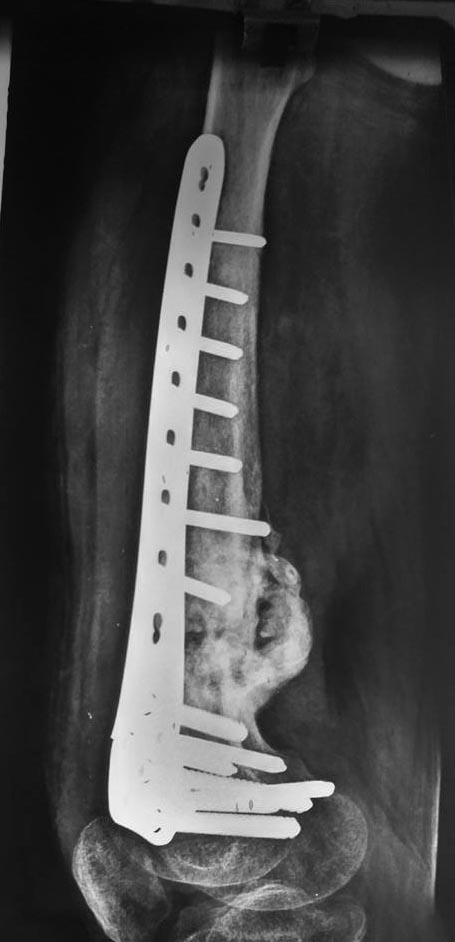

Боковая проекция.

с таким "ежом" можно бы ожидать атрофического ложного сустава, а здесь есть элементы гипертрофичесого + винты не все расшатались+полости+склероз, уверен, что гниет, после обработки вполне может и под маскулет подойти.

гниет скорее всего

Методика хорошая, но она для дефектов. А здесь больше похоже на асептическое несращение, так что техника Masquelet избыточна.

Можно минимально инвазивно убрать пластину и сделать антеградный остеосинтез. Гвоздь на всякий случай с антибактериальным покрытием. Зону несращения пройти развертками.

Ну малоинвазивно удалить пластину тут вряд ли получится. Плюс при ретроградном введении стержня зону перелома хотите или нет придется визуализировать- развертками через канал тут не пройти.